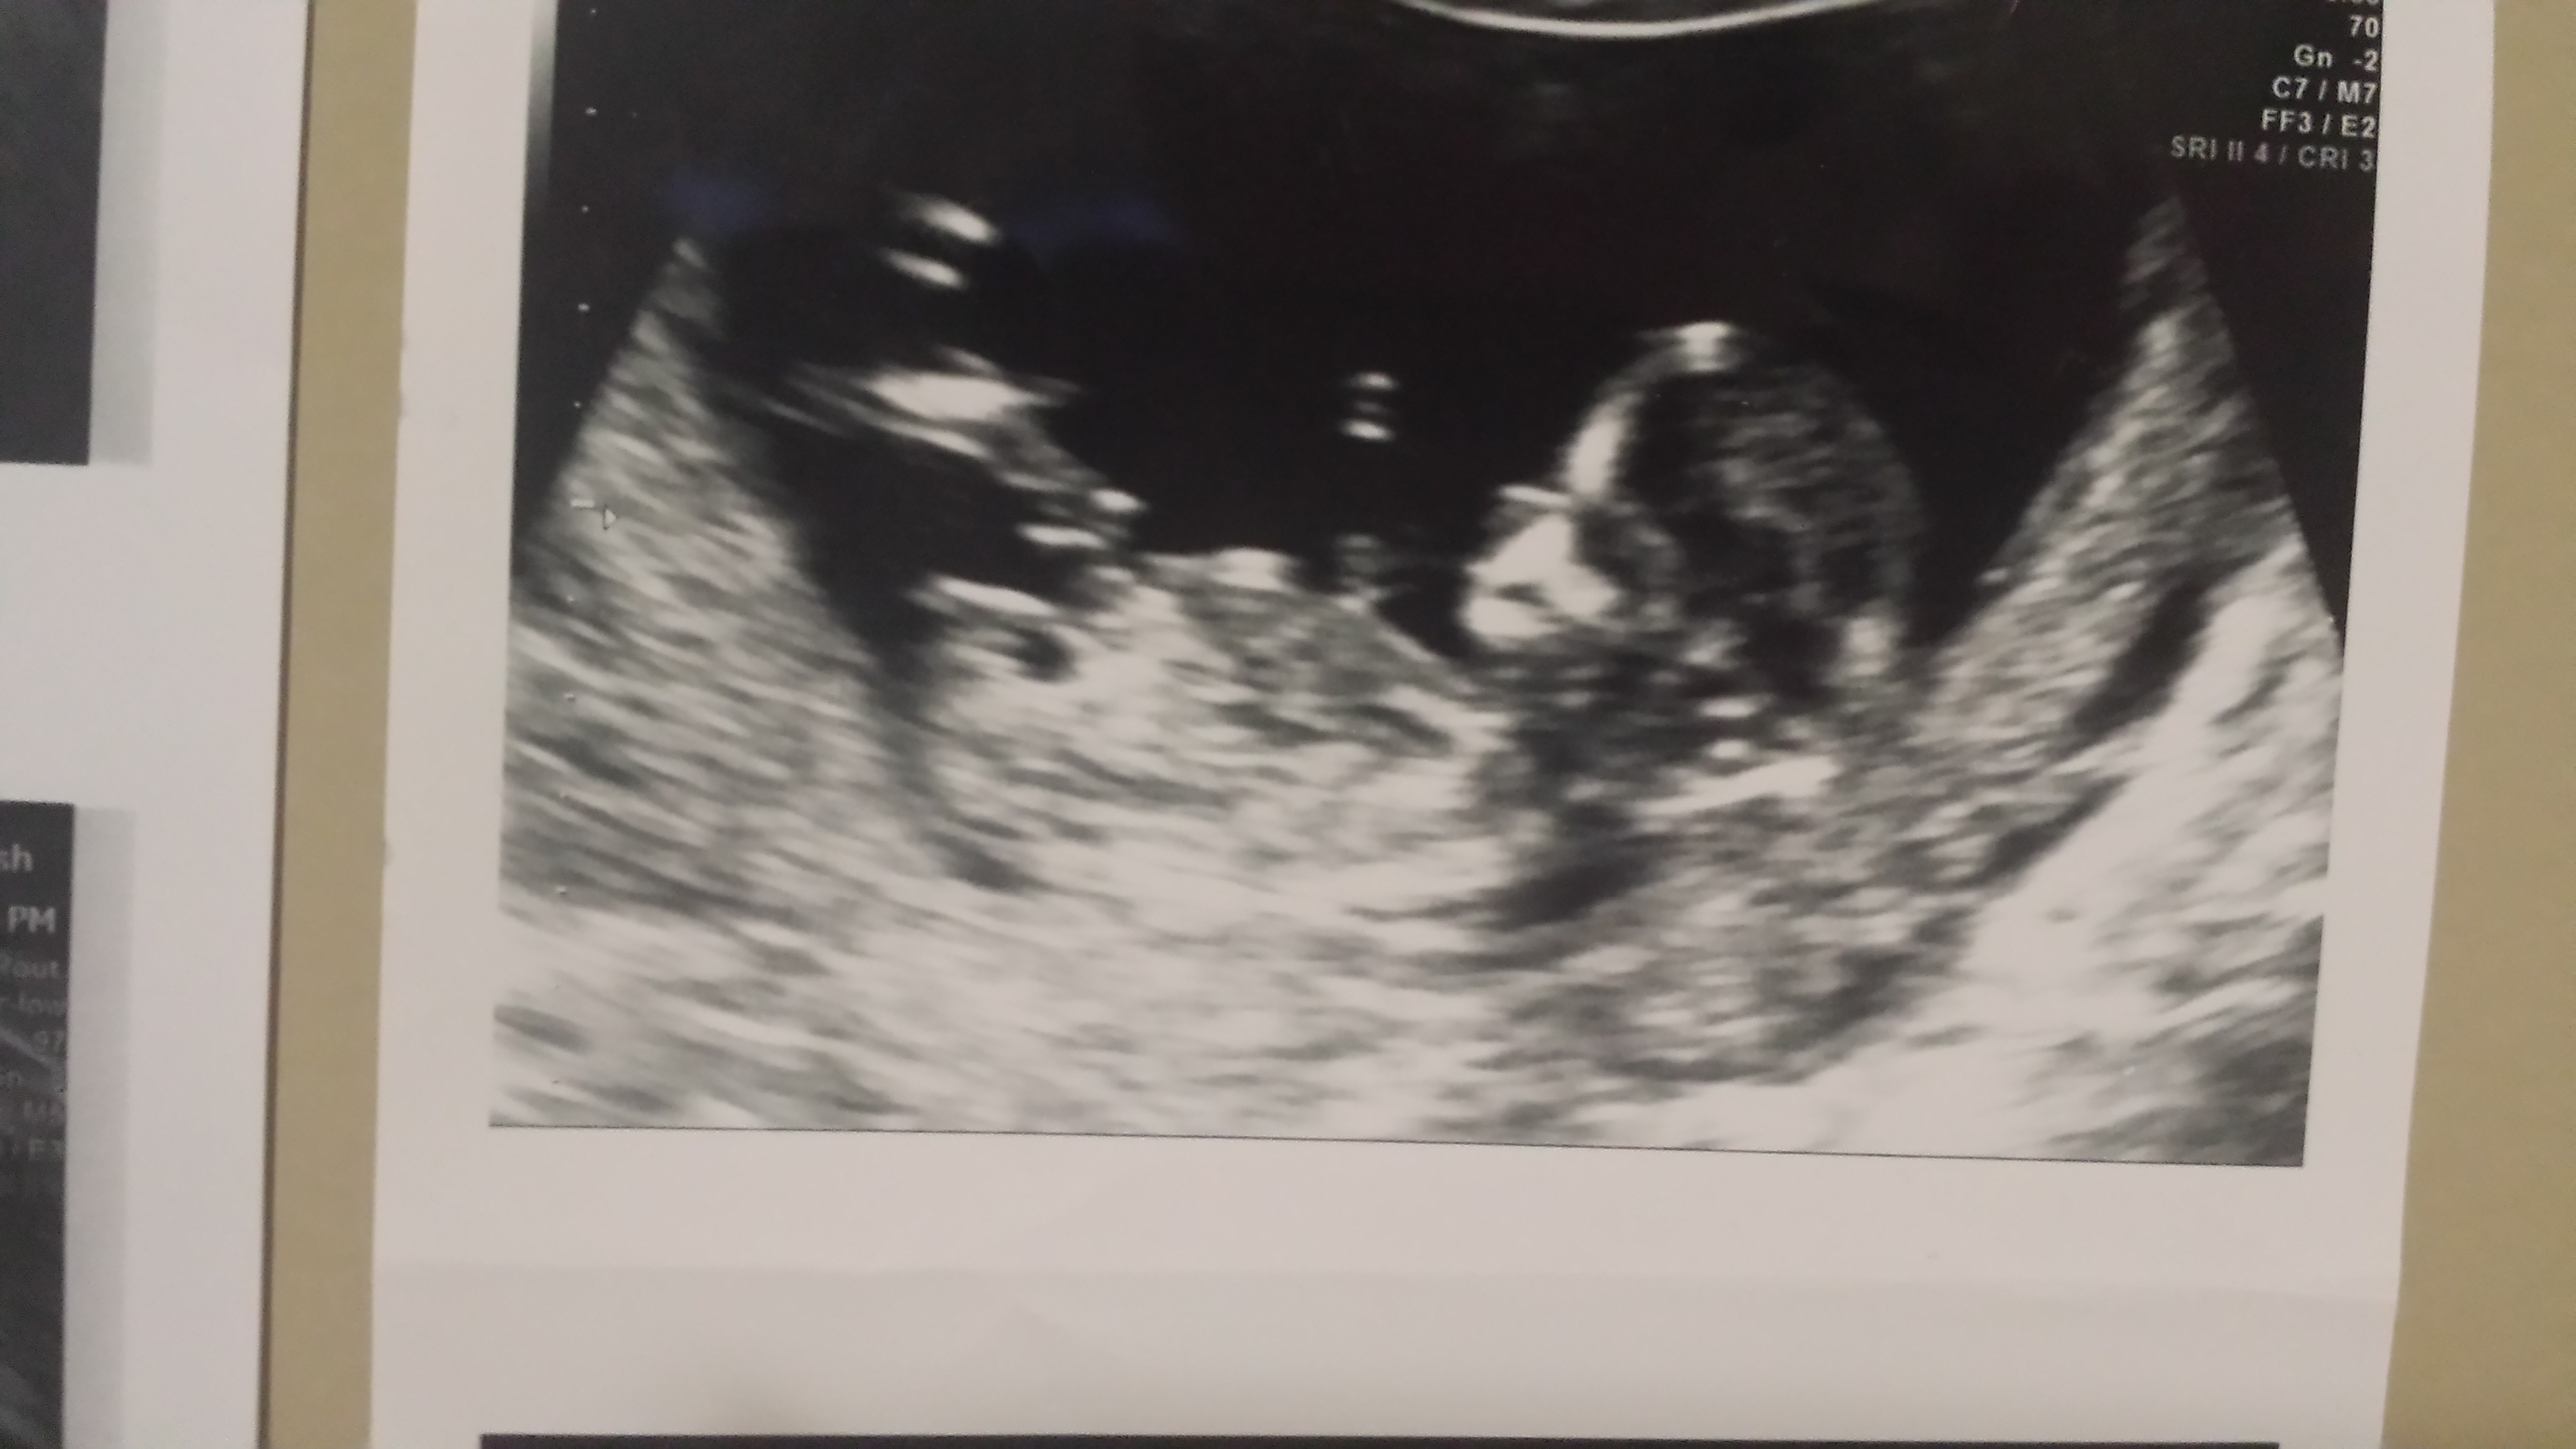

I had a ultrasound done at 13weeks and the tech said if she had 2 guess that she would guess girl. Ofcourse that got me excited but i know its still very early. Can u all tell me if u think shes right or wrong?

Attachment 21135

Heres another 1

That's a girl nub :)

P.s even I can see that's classic girly nub!! Big congrats I would be pretty confident about that!!